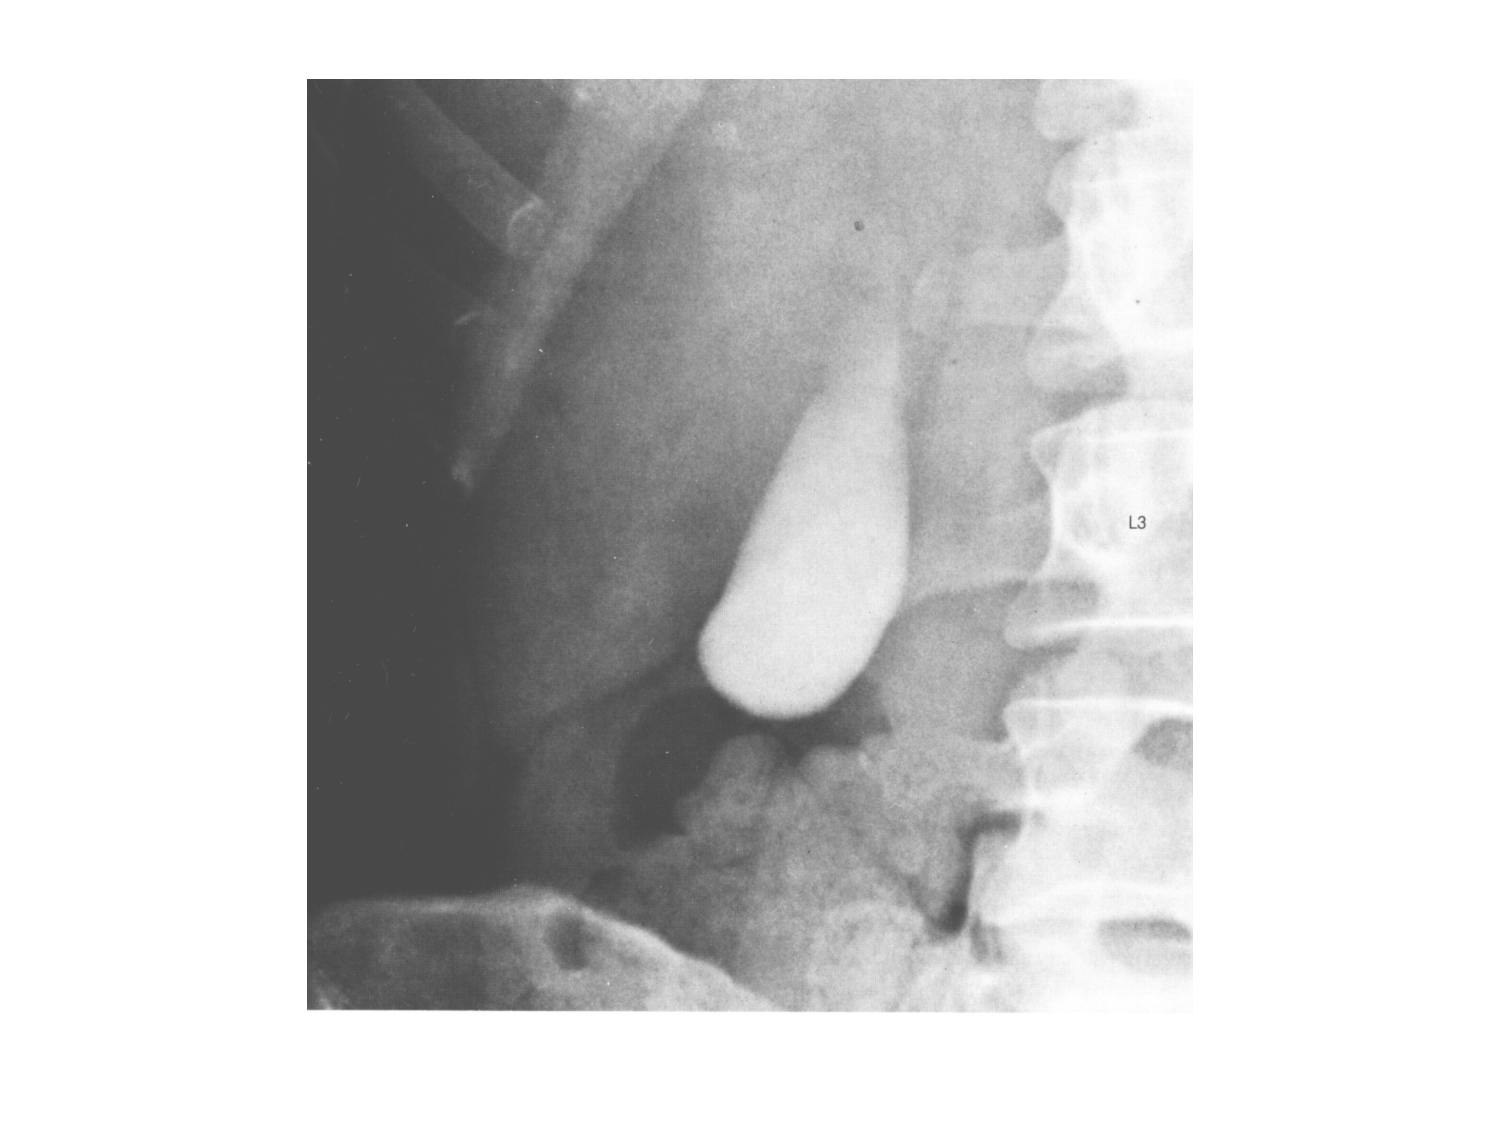

11.35 · Abdomen gros intestin foie rate pancreas vascularisation

Abdomen gros intestin foie rate pancreas vascularisation